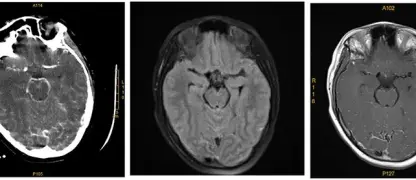

Clinical pictures of lymphatic filariasis